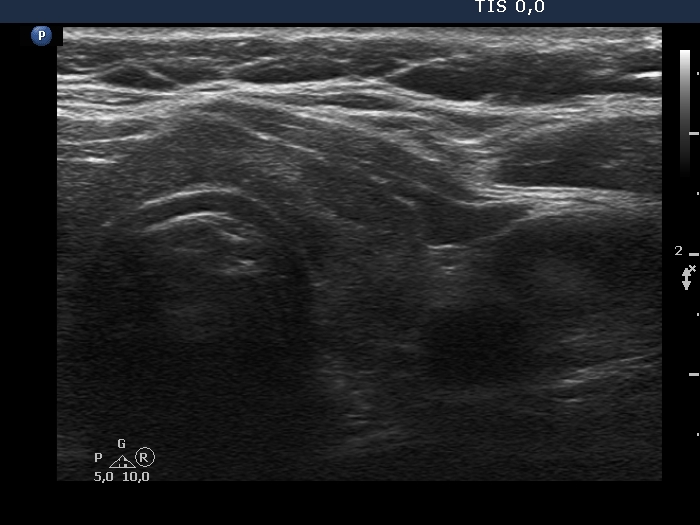

Examination in 2018 (second row of images):

Clinical data. The patient came to a routine follow-up. She had no complaints.

Palpation: unchanged.

Laboratory test: TSH 0.36 mIU/L on daily 125 microgram levothyroxine.

Ultrasonography. Except for the lesion which was previosuly cytologically investigated, the pattern remained unchanged. The lesion in question became cystic and was composed of two chambers. In the tissue part separating the two chambers, hyperechoic granules have appeared. These were mostly related to ventral cystic areas, therefore, they should be regarded as back wall figures.

We recommended that she takes the replacement therapy at the same dose and has a TSH scan after half a year and an ultrasound scan after two years.